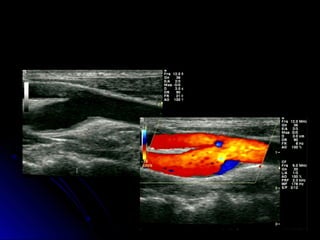

Exame normalExame normal

Paredes arteriais regulares, diâmetros normais,Paredes arteriais regulares, diâmetros normais,

luz anecóide.luz anecóide.

Mapeamento colorido anatômico.Mapeamento colorido anatômico.

Padrão espectral habitual, sem borramentos.Padrão espectral habitual, sem borramentos.

Velocidades sistólicas dentro de faixas normais.Velocidades sistólicas dentro de faixas normais.